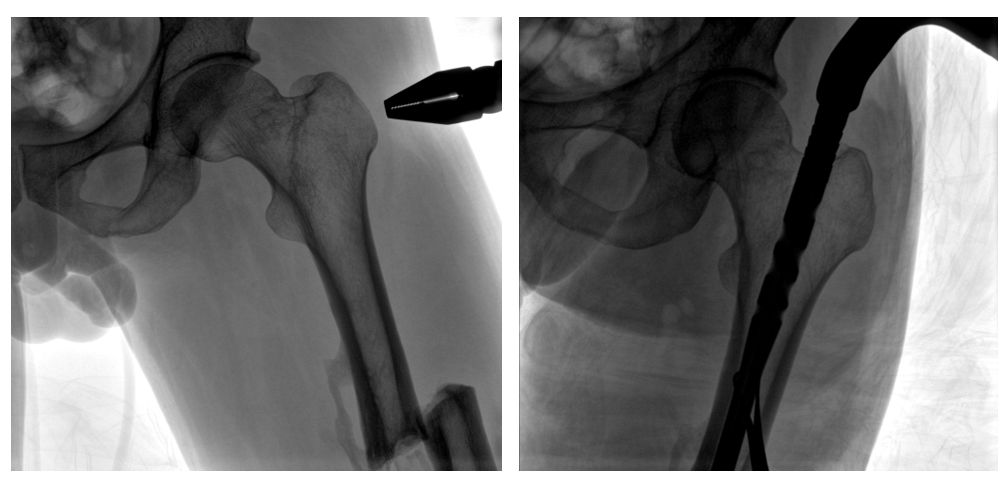

普愛醫療PLX119C大平板一體式C形臂采用30CM×30CM的平板探測器,在脊柱和長骨骨折等骨科手術治療中,獲取更大視野、更清晰的骨折部位圖像,能夠有助于醫生在術中及時了解和評估骨折部位的對位、對線情況,且能進行長度和角度測量,為進一步提高手術質量提供強有力的支持。